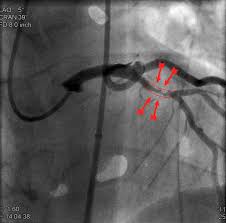

Slideshow widow maker secretary

Widow maker

secretary en.wikipedia.org